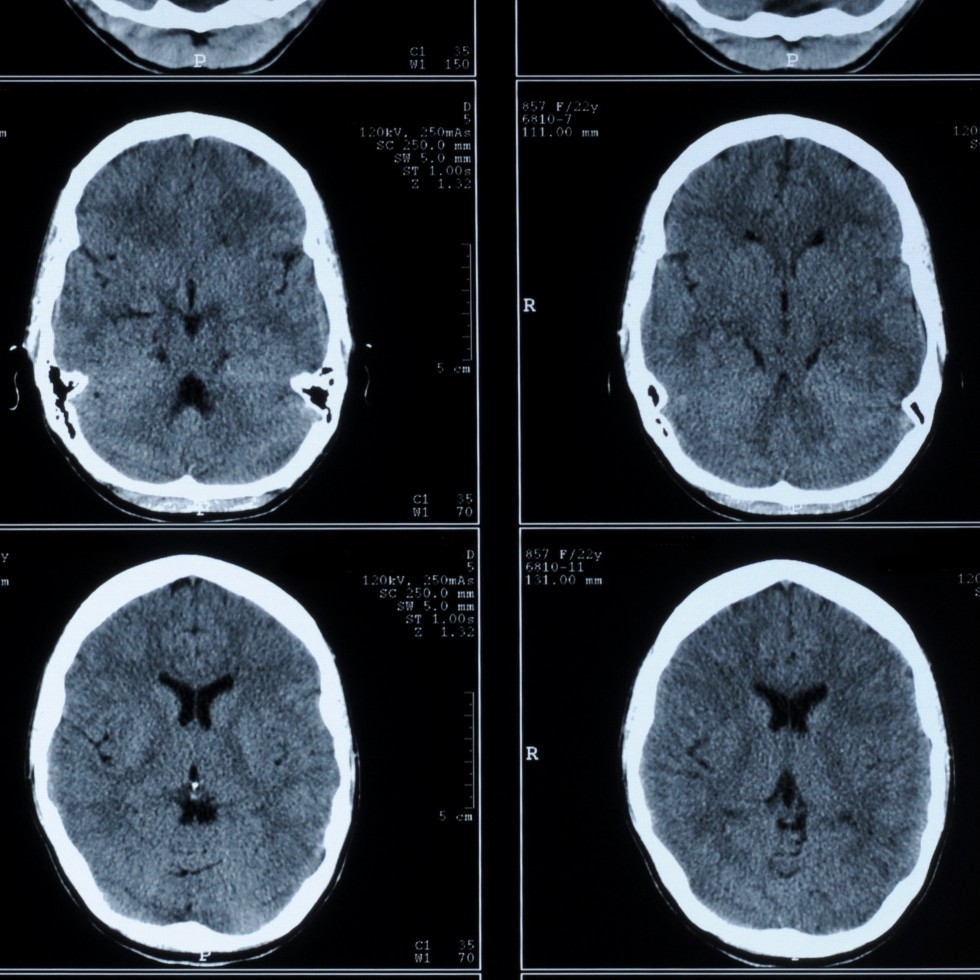

Head CT

A CT scan is a type of scan that uses special X-ray equipment to obtain images from all angles of the body. It then joins the images together to show a cross-section of body tissues and organs. The scan provides detailed information on the scanned part of the body.